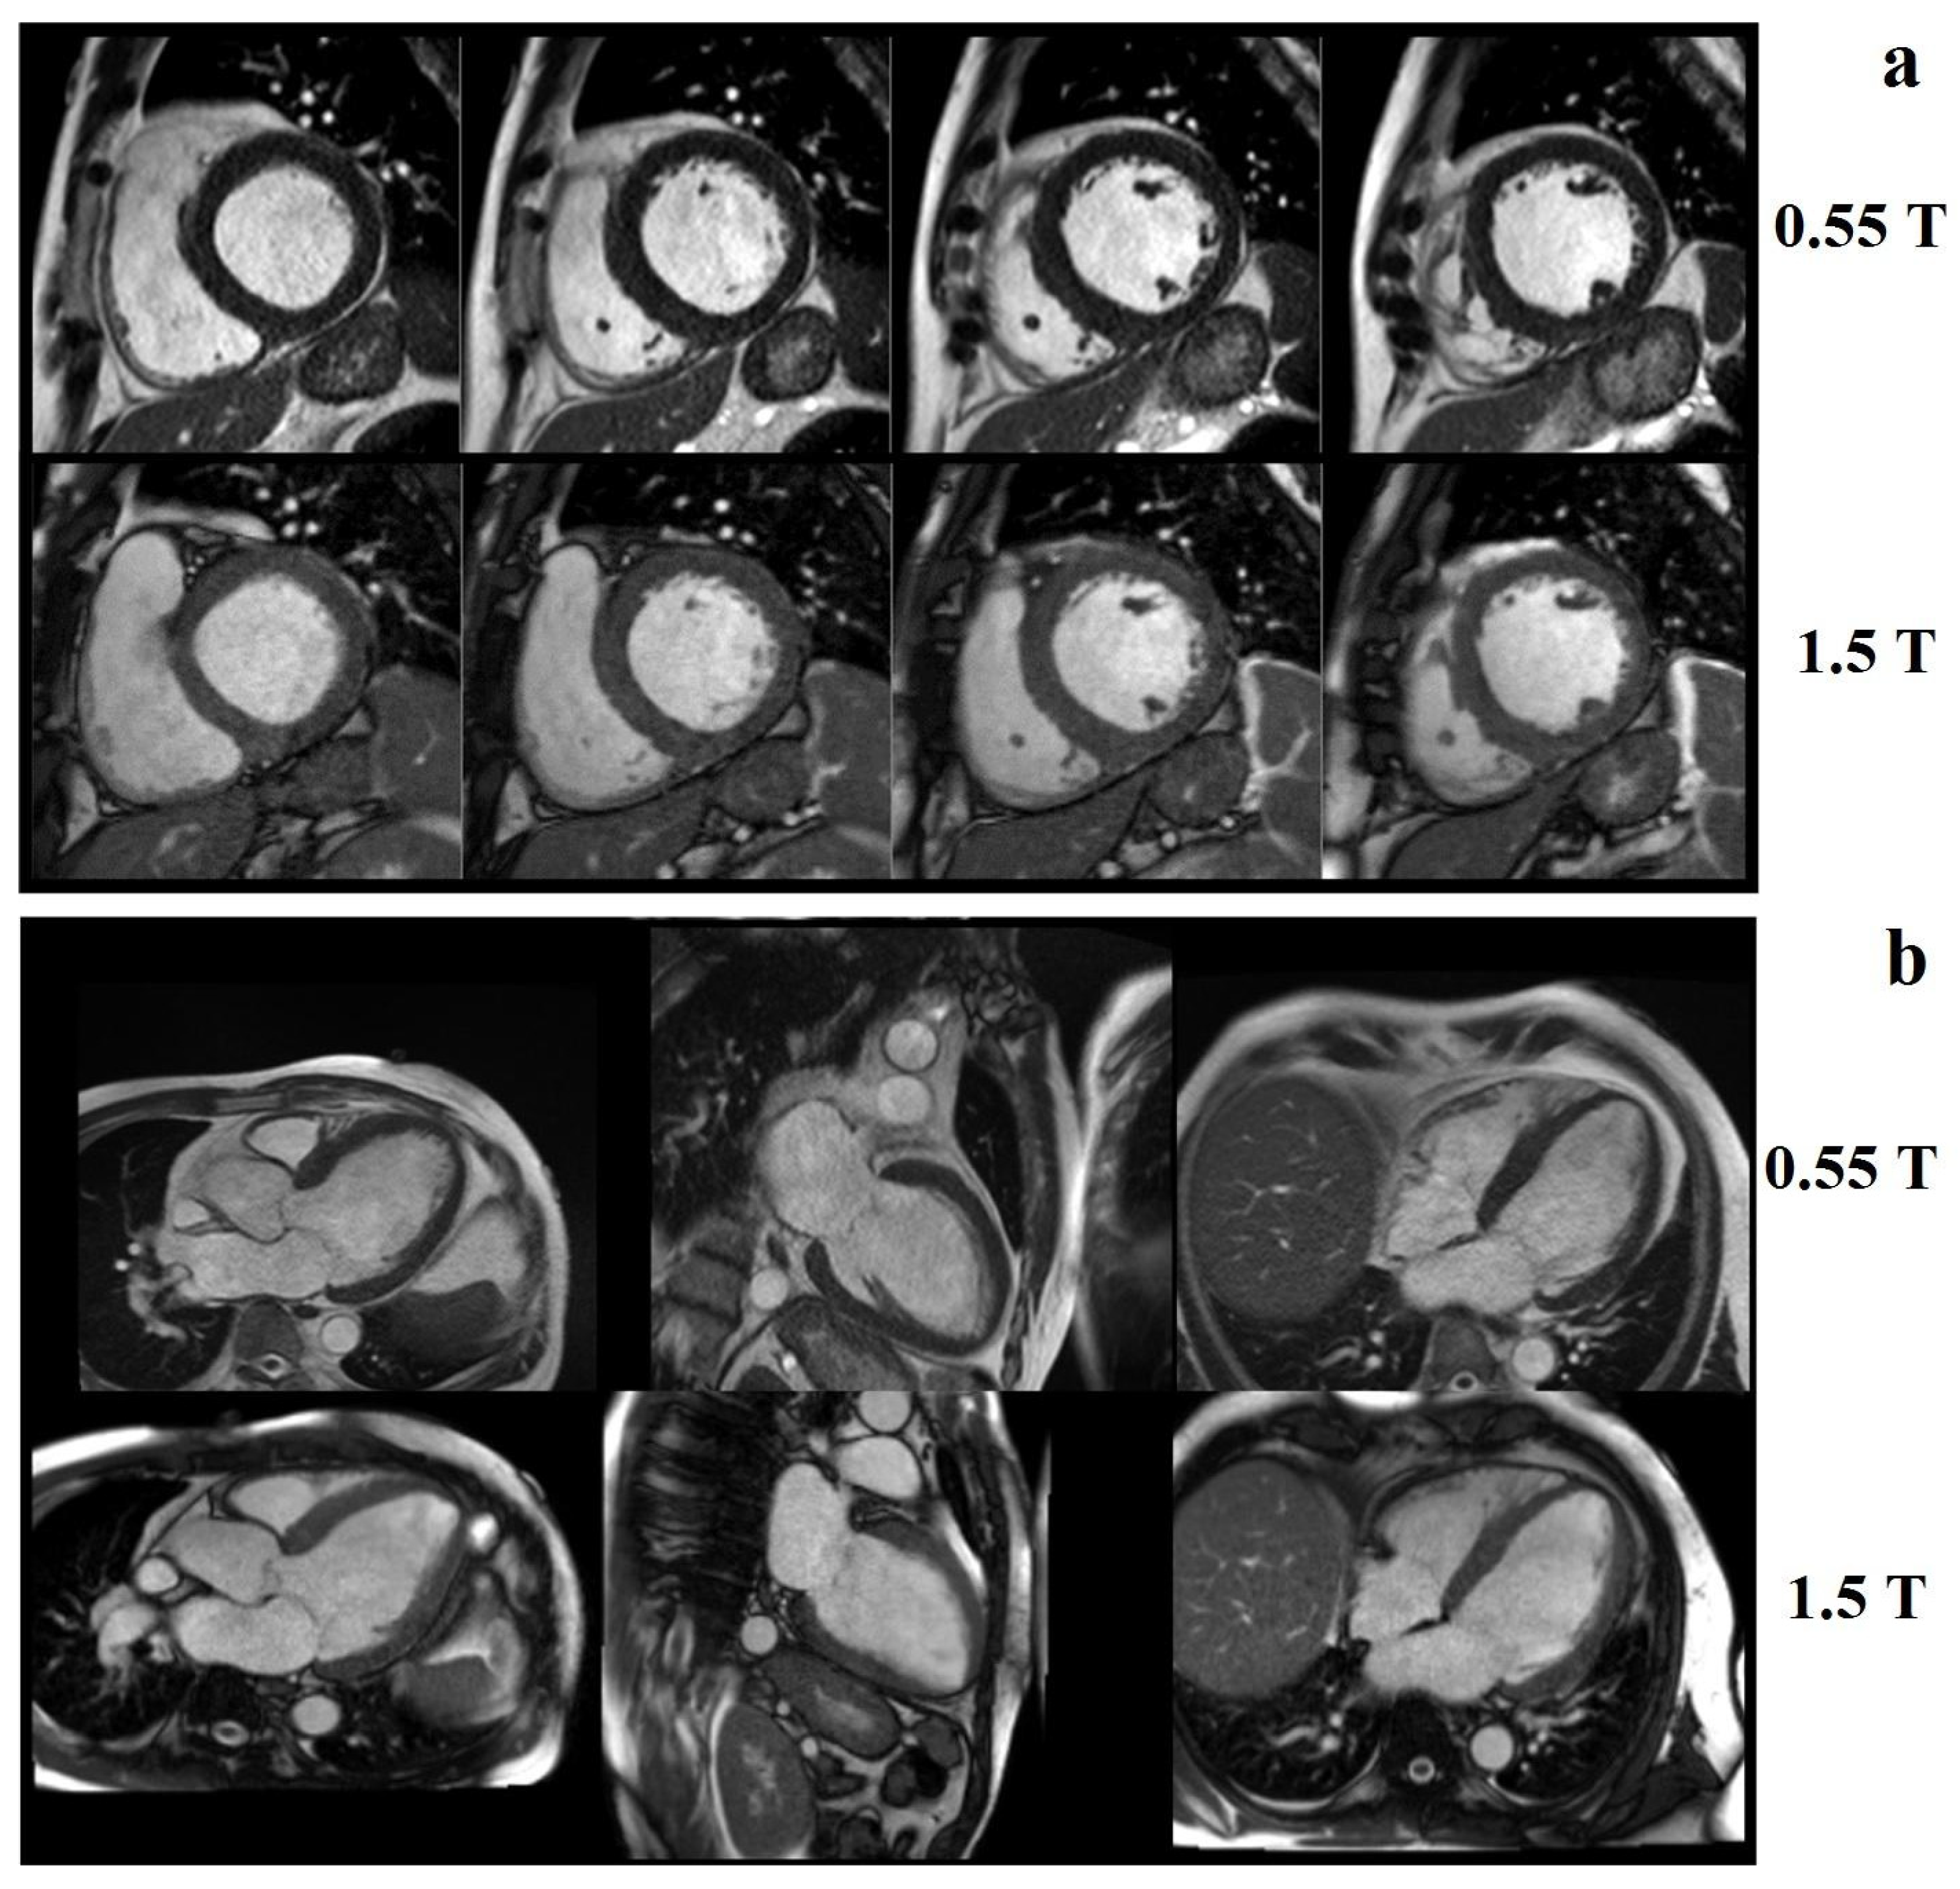

Low-field MRI has received increasing attention since low-field MR images have been shown to be diagnostically equivalent to 1.5 T images for specific applications [47]. Bandettini at al. [48] demonstrated that, by using a high-performance 0.55 T cardiovascular MRI system, it is possible to obtain good image quality, cardiac function, and quantification of volume compared to a standard 1.5 T scanner (Figure 10).

Figure 10.

Examples of image quality at 0.55 T and 1.5 T breath-held, cine-steady, state-free precession: (a) short axis and (b) long axis slices from a patient with a nonischemic cardiomyopathy. Reprinted from [48].